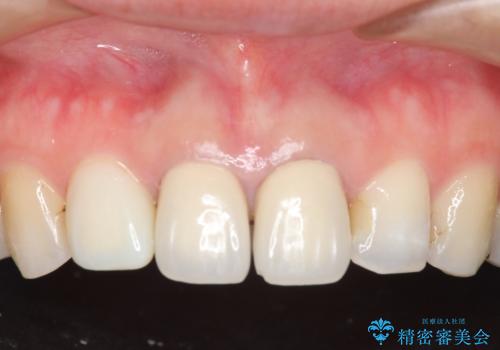

- 上顎の前から2番目の歯の古い樹脂をセラミックにしたいといらっしゃった方の症例です。

古い樹脂を除去後、オールセラミッククラウンによる補綴を行いました。

今回用いたオールセラミッククラウンはジルコニアフレームという白い素材の上にセラミックを盛っているため、審美性が非常に高いのが特徴です。